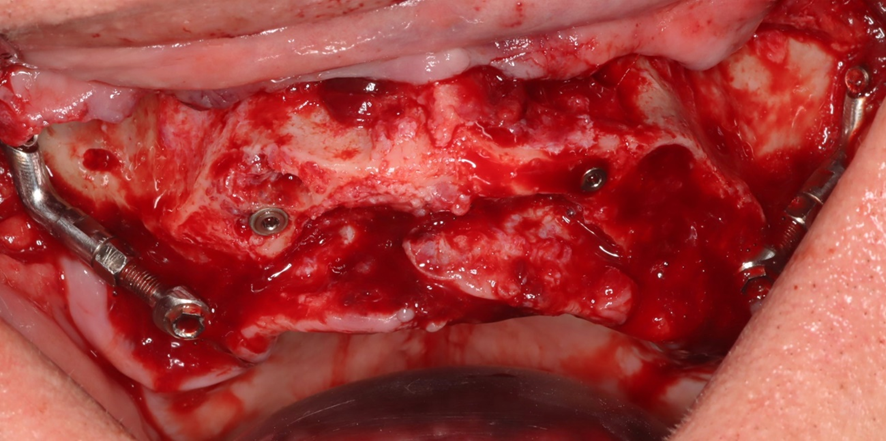

A montagem do Pilar Z exige do cirurgião-dentista habilidade e curva de aprendizado. Nem sempre se consegue adaptar o Pilar Z sem interferências ósseas. Por essa razão, adotamos uma rotina de instalação dos pilares na prototipagem, simulando assim, uma situação muito próxima do real no procedimento cirúrgico.

Desta forma, pode-se observar possíveis contatos ósseos no corpo da maxila ou do zigoma que não permitam o assentamento passivo do Pilar Z.

Conseguimos orientar a plataforma do Pilar Z através da chave de alinhamento, para assentamento passivo da prótese. A visualização do local de emersão do Pilar Z junto ao rebordo alveolar nos indicará onde realizar a osteotomia para confeccionar o “nicho” que abrigará a plataforma do mesmo.

O posicionamento, junto ao rebordo alveolar, das plataformas dos Pilares Z, deverá ser aproximadamente próximo ao 16/26 para distais e próximo ao 12/21 para mesiais, configurando assim o polígono de Roy.